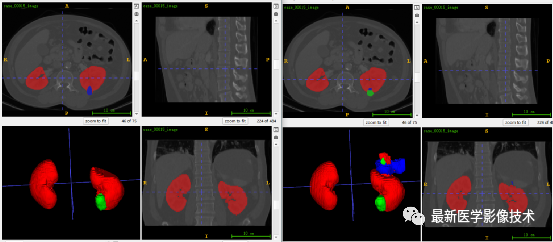

肾脏、肾肿瘤和肾囊肿分割

1、首先根据mask得到肾脏ROI范围,然后根据ROI从原始图像和mask提取ROI区域。

2、分析ROI图像,得到图像平均大小是46x129x294,因此将图像缩放到固定大小240x256x256。图像预处理,对步骤1的ROI图像进行(-200,400)窗宽窗位截断,然后采用均值为0,方差为1的方式进行归一化处理,再将数据分成训练集和验证集,对训练集进行2倍数据增强。

3、搭建VNet3d网络,使用AdamW优化器,学习率是0.001,batchsize是1,epoch是300,损失函数采用多类别的dice和交叉熵。

4、训练结果和验证结果